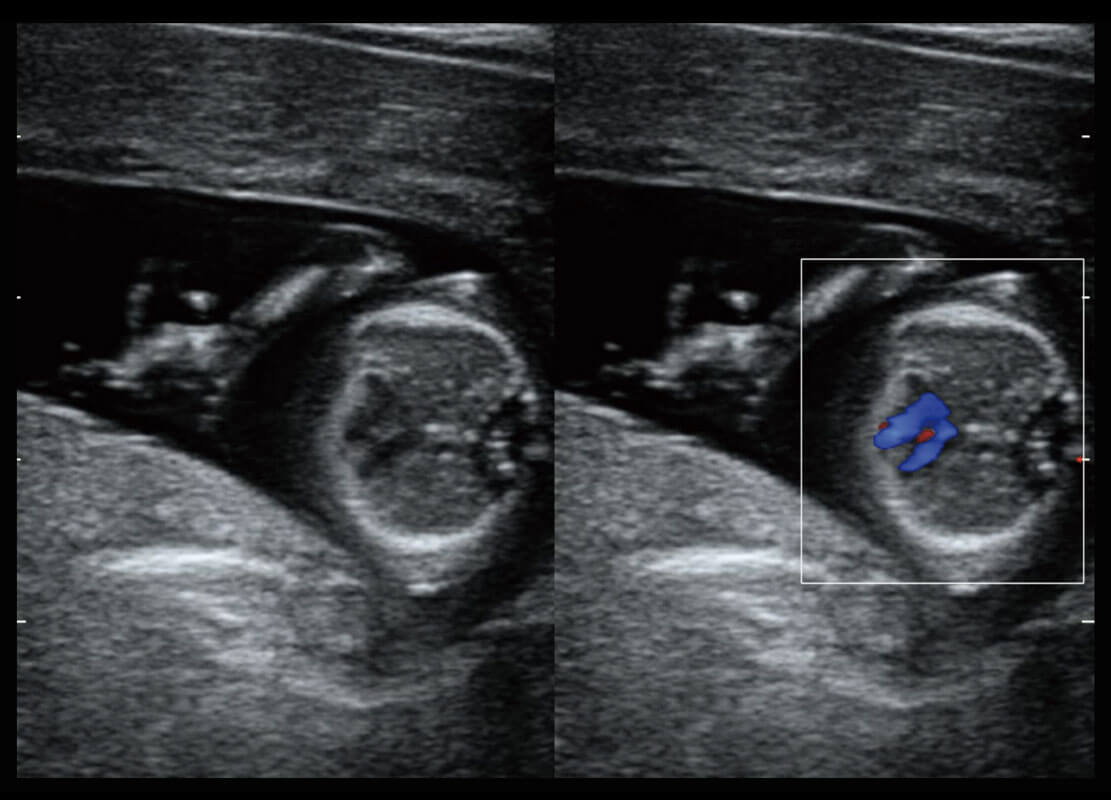

腔内妇科-宫腔分离

腔内妇科-卵巢

腔内三维-宫内节育器

腔内三维-光影成像